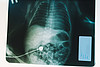

05122022-69.